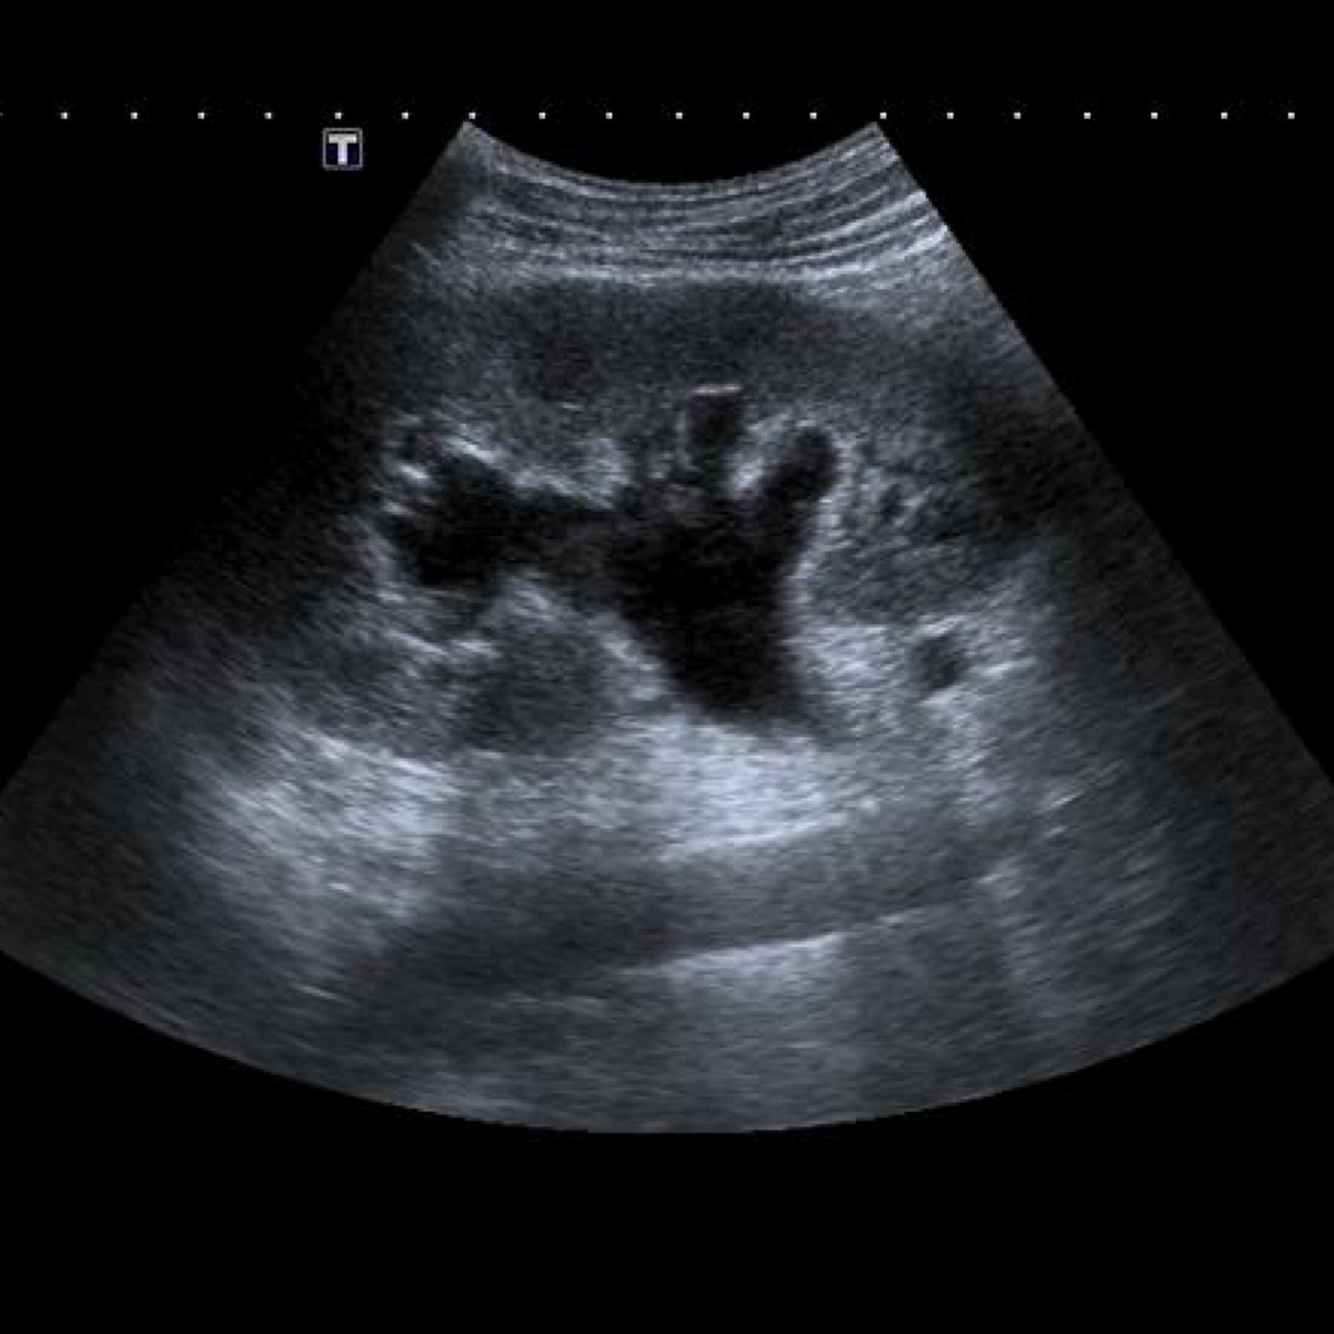

Q

The image represents what?

A

Dilated calyces and renal pelvis